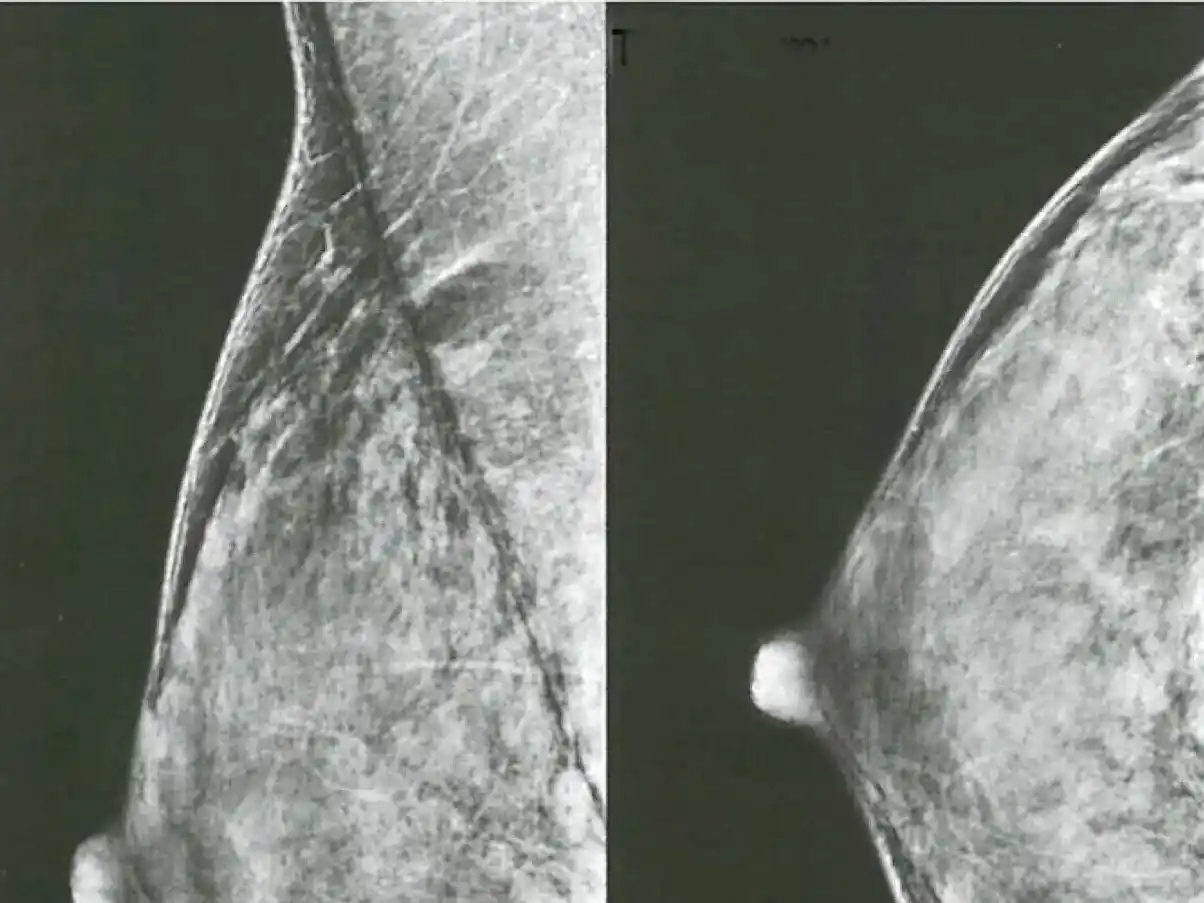

Cáncer de mama

La IA mejora la detección de cáncer con mamografía en un estudio en 500.000 mujeres.

Un innovador estudio multicéntrico realizado en 12 centros de detección en Alemania ha demostrado que el uso de inteligencia artificial (IA) en mamografías de doble lectura aumenta las tasas de detección de cáncer de mama en un 17,6 %. La investigación, centrada en mujeres de entre 50 y 69 años, comparó el rendimiento de la lectura tradicional con la asistencia de IA, evidenciando un impacto positivo significativo en los programas de cribado.